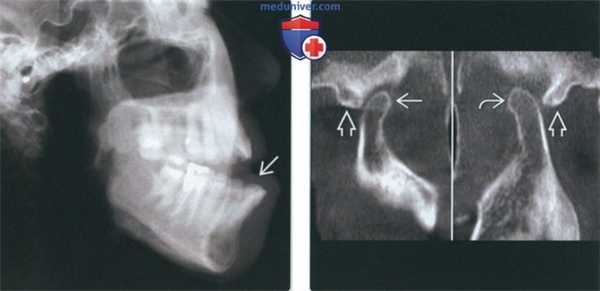

(Слева) На рентгенограмме в боковой проекции у этого же пациента определяется прогнатическое положение нижней челюсти и открытый передний прикус вследлвие передне-верхнего смещения мыщелков нижней челюсти.

(Справа) На сагиттальной КЛКТ правого и левого мыщелков у этого же пациента определяется, что мыщелки расположены спереди и сверху относительно сулавных возвышений. Обратите внимание, что мыщелки имеют нормальную форму, а кортикальная плалинка не изменена.